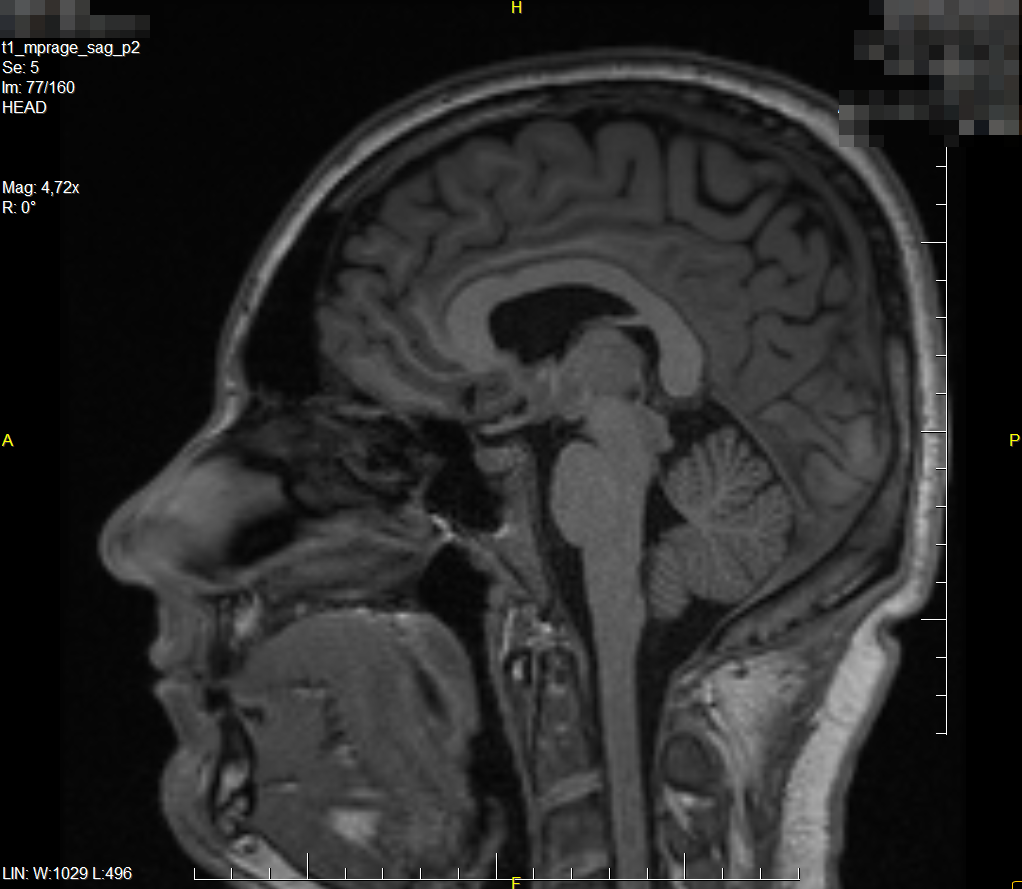

@nezka92 zdjęć, na których widać, że jest wszystko ok, mam kilka (i to jest jedno z nich). Z innej perspektywy są pewne widoczne zmiany, których być nie powinno. Celem leczenia jest opóźnienie, a najlepiej całkowite zatrzymanie postępu, czyli pojawiania się nowych zmian w mózgu. Nie ma w tej chwili sposobu, aby takie zmiany już powstałe, wyleczyć. Gdyby zaczęły pojawiać się nowe to z pewnością odczułbym to np. zmianą temperatury skóry, jakimś niedowładem w ręce/nodze. Nigdy tak nie miałem i obym nie miał

@LukB już sam nie wiem na ile pytasz poważnie, a na ile zacząłeś już sobie robić jaja z tematu, ale odpowiem. Wszystko jest na NFZ, mam za⁎⁎⁎⁎⁎tych lekarzy, leki warte parę k miesięcznie za free, komplet badań co 3 miesiące, rezonans (czyli zdjęcie mózgownicy) raz w roku. Już 5 lat z tym żyje i nic mi nie jest

A tak poza tym to jeszcze rozwinę trochę temat samego SM. W okół tego badziewia narosło wiele mitów, bo kojarzy się to głównie tylko z wózkiem. Kiedyś tak było, bo nie było dobrej diagnostyki i to stawiano tylko ludziom, którzy mają naprawdę widoczne ubytki neurologiczne. Teraz się w miarę szybko wykrywa no i leczy. Łażąc do szpitala co 3 miesiące poznałem sporo ludzi, którzy z tym żyją wiele lat i funkcjonują całkowicie normalnie. I nie jest to aż tak rzadka przypadłość, bo w Polsce żyje z tym 50k ludzi, a pewnie jest jeszcze więcej, bo ludzie po prostu przechodzą to naprawdę łagodnie (tak jak np. ja).